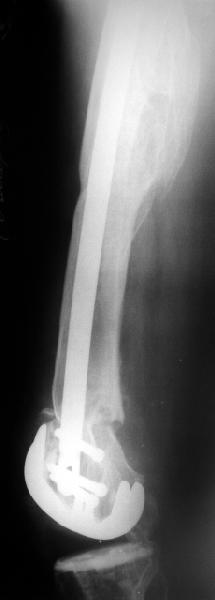

Alexander Chelnokov 02 Июнь 2004, 13:45

В итоге сделали антеградный остеосинтез. В дистракторе свежий перелом вправился сразу, а вот старый - оставил проблему, дистальный отлмомк остался все равно кзади. И гвоздь бы прошел кпереди от него, а ретроградный - перфорировал бы передний кортекс. Так что пришлось еще сделать чрескожную остеотомию через перелом, чтобы малость мобилизовать дистальный отломок. Снимки в прилжении.

Критика, комментарии, мнения?

The radiographs look excellent and a good outcome would be anticipated. The idea to osteotomize the femur shaft to compensate for the prior shaft malunion was clever and should work fine.

I can't actually see the osteotomy on either radiograph. Is it more proximal than we see in these radiographs or so well aligned as to be not visible?